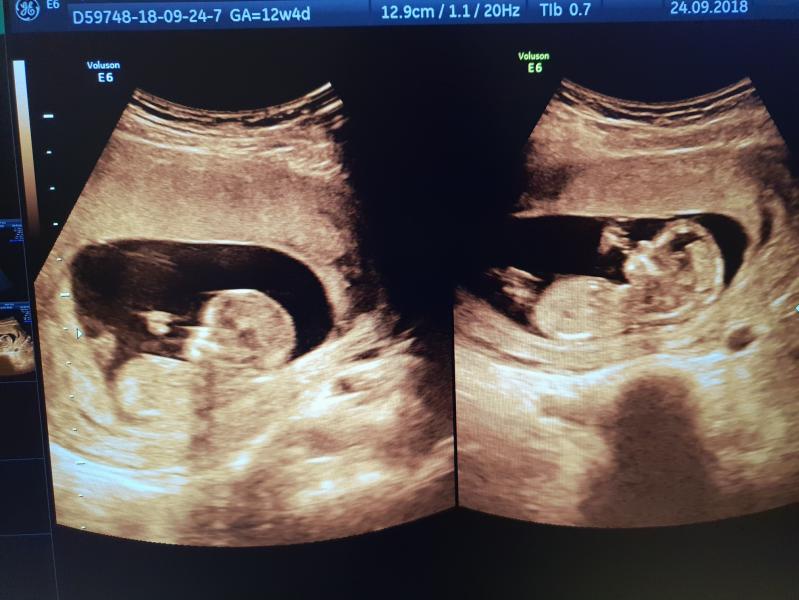

А сегодня у нас был скрининг в ЖК 3 Южное Бутово, по направлению, врач уже многим известная здесь Григорьянц Ева Рачиковна😍 Божечки, какая же она потрясающая!!! Я приехала с мамой, она очень хотела увидеть малышей, а то все мужу дают смотреть🤣 Я зашла в кабинет ровно по записи и тихонечко попросила разрешить пустить маму. Договорились, что сначала вдвоем поговорим об анамнезе, а потом она сама позовет маму. Так и было, позвала☺ Мама, конечно, чуть не зарыдала. Врач обалденная, все время рассказ...